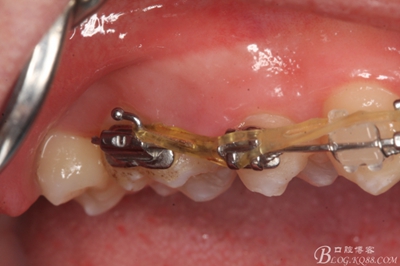

圖1.術前患者的口內(nèi)照片:16與14之間有約2mm間隙,矯治器已經(jīng)安裝到位。